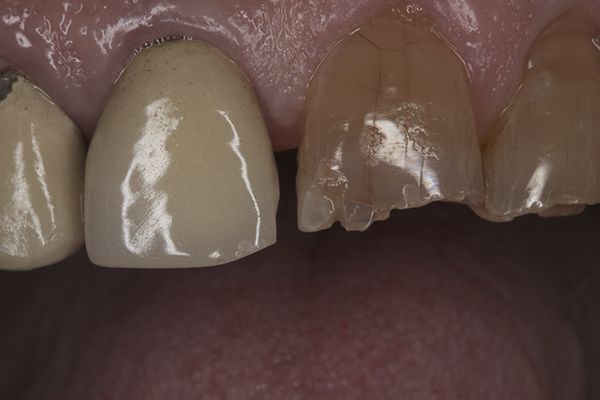

(12.) Preoperative right anterior, close-up view.

Figure 12

(13.) Preoperative anterior, close-up view.

Figure 13